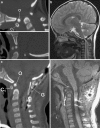

Background: The embryology of the bony craniovertebral junction (CVJ) is reviewed with the purpose of explaining the genesis and unusual configurations of the numerous congenital malformations in this region. Functionally, the bony CVJ can be divided into a central pillar consisting of the basiocciput and dental pivot and a two-tiered ring revolving round the central pivot, comprising the foramen magnum rim and occipital condyles above and the atlantal ring below. Embryologically, the central pillar and the surrounding rings descend from different primordia, and accordingly, developmental anomalies at the CVJ can also be segregated into those affecting the central pillar and those affecting the surrounding rings, respectively.